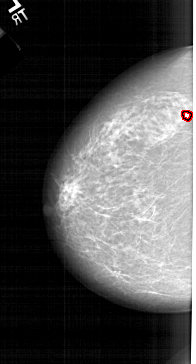

A_1214_1.LEFT_CC

FILE: A_1214_1.LEFT_CC.OVERLAY

TOTAL_ABNORMALITIES 1

ABNORMALITY 1

LESION_TYPE CALCIFICATION TYPE PLEOMORPHIC DISTRIBUTION CLUSTERED

ASSESSMENT 4

SUBTLETY 4

PATHOLOGY MALIGNANT

TOTAL_OUTLINES 1

BOUNDARY